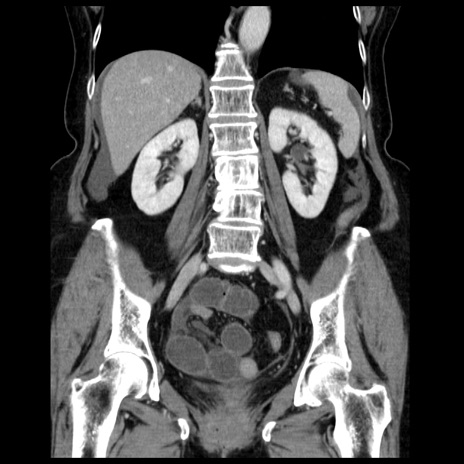

症例13(冠状断像)

【症例】70歳代女性

【主訴】腹痛、嘔吐

【現病歴】15時間程前(昨晩)より腹痛あり。今朝になっても症状の改善なく、嘔吐あり。腹痛も増悪あり、救急外来受診。

【既往歴】子宮癌全摘術後

【身体所見】意識清明、BP 121/72mmHg、P 74bpm、SpO2 100%(RA)、腹部:平坦・軟、腸雑音ほぼ聴取せず。下腹部・心窩部・臍左上に圧痛あり。反跳痛なし。

【データ】WBC 10600、CRP 0.15